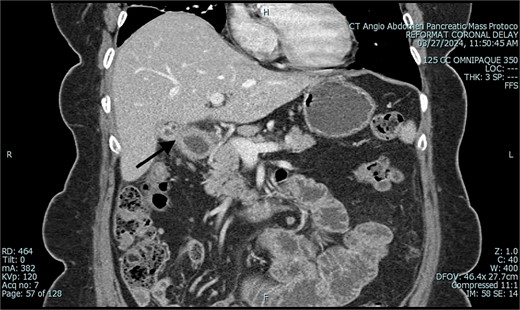

Over the course of the operation, the patient became septic and was started on vasopressor support. Her surgery was expedited by leaving the bowel in discontinuity and placing a wound vac for temporary abdominal closure. After stabilization, she returned to the operating room on hospital day 7 for bowel anastomosis and definitive abdominal closure. She recovered well postoperatively and was discharged home on hospital day 18. Follow-up computed tomography (CT) revealed a cholecystoduodenal fistula (Fig. 9). Elective surgery for cholecystectomy and fistula repair is being considered.

Postoperative CT of abdomen in coronal view, demonstrating suspected cholecystoduodenal fistula.